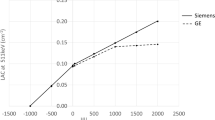

In order to determine the number of OSEM iterations allowing the comparison of the two cameras under similar convergence conditions, an IEC torso phantom was performed on both systems following the NEMA NU-2 2012 protocol (i.e. with 5.3 MBq/L in the background and a 4:1 sphere-to-background ratio) and reconstructed with 10 subsets and a number of iterations ranging from 1 to 10 for digital and from 1 to 15 for analog cameras, respectively. The convergence of the contrast recovery coefficient of the smallest 10-mm hot sphere was chosen as a convergence criterion for this study. As detailed in Fig. 1, where contrast recovery coefficients are plotted according to the relative noise (coefficient of variation in the background), this convergence was reached at about 5 iterations on the digital PET with either a 2-mm or 1-mm voxel size and about 10 iterations on the analog PET. Consequently, OSEM reconstructions were performed with 3 iterations and 15 subsets and 3 iterations and 33 subsets, respectively, for digital and analog cameras.

Contrast recovery coefficients determined in percentages for the 10-mm hot sphere, with 2-mm voxel size for analog and digital PET and with 1-mm voxel size for digital PET and displayed according to relative noise (coefficient of variation in the background, in percentages) for each number of iterations. Black symbols and dashed arrows represent the numbers of iterations considered to reach sufficiently high levels of convergence. This convergence was reached at 5 iterations for the digital PET with either 1-mm or 2-mm voxels size and at 10 iterations for the analog PET

It should be emphasized that these differences in image contrast, noise, and spatial resolution were documented through optimization of the reconstruction processes in order to reach a high level of convergence for the contrast recovery coefficient for each camera and according to voxel size. This level of convergence was reached with a much lower number of iterations with the digital PET as opposed to the analog PET as evidenced in Fig. 1, a current observation due to the higher temporal resolution of the digital PET camera [17, 18].